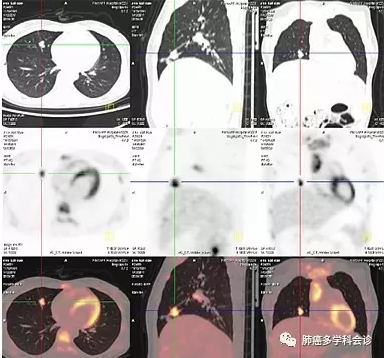

脑 MRI 提示脑多发转移